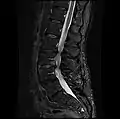

MRI lumbar spine with degeneration, post-hemilaminectomy L4-5 (sagittal FAST STIR)